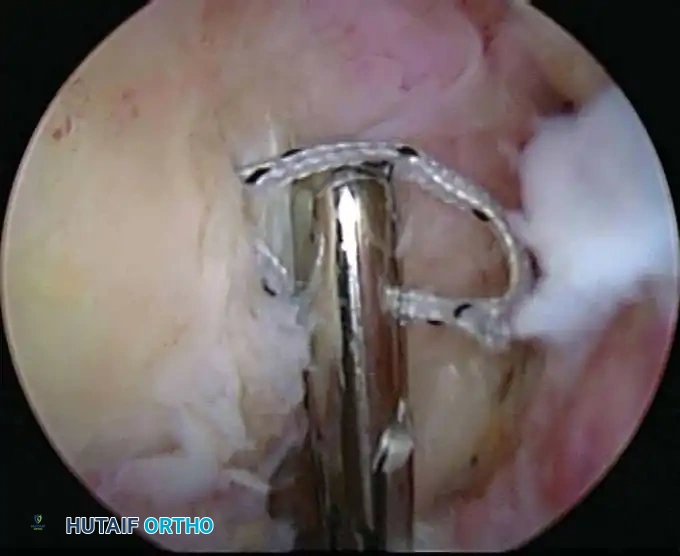

Once diagnostic evaluation is complete and hemostasis is secured, the therapeutic phase commences. Whether performing a SLAP repair, a Bankart stabilization, or a rotator cuff repair, the principles of tissue mobilization, anatomical footprint restoration, and secure biomechanical fixation remain paramount.

Modern arthroscopy relies heavily on suture anchors (biocomposite or all-suture constructs) and advanced arthroscopic knot-tying or knotless techniques. The ability to pass sutures through retracted, fibrotic tissue and secure them under appropriate tension without strangulating the microvascular supply is the hallmark of a master arthroscopist.

* Instability/Labral Repairs: Immobilization in a sling (often with a small abduction pillow) for 4 to 6 weeks. External rotation is strictly limited to protect the anterior capsulolabral repair.